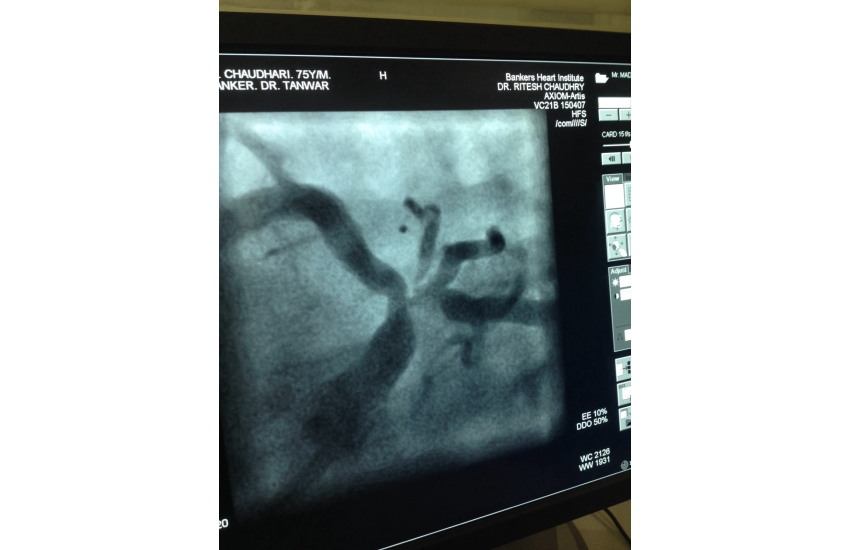

75 years old male presented with unstable angina undergone CAG which is shown LMCA bifurcation lesio

29 Dec 2015